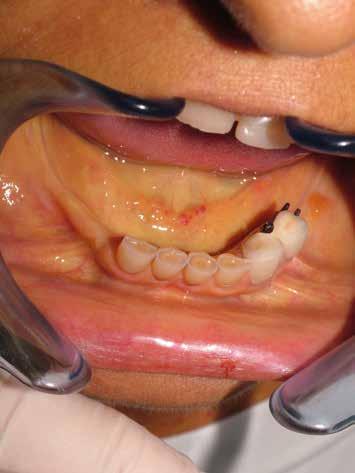

Il paziente del seguente caso, già visitato nel 2019, è poi tornato nel 2021 per una rivalutazione. Già durante la prima visita era stata rilevata una situazione di compromissione generale, sia dal punto di vista igienico, sia funzionale.

Alla visita di rivalutazione è emerso un ulteriore peggioramento della situazione, confermata anche dall’esame radiografico, con parodontopatia, sanguinamento al sondaggio, infiammazione diffusa, alitosi, difetto parodontale verticale mesiale a 2.3, residui radicolari 1.4, 1.6, 1.7, 3.6, 3.8 e carie destruenti di 1.5, 2.6, 3.5, 3.7 (con lesione endoperio) e 4.7 con estrusione e carie (Figg. 1, 2)

Si è consigliato di procedere per gradi, con bonifica di tutti gli elementi malati e irrecuperabili e successivamente sostituire gli elementi mancanti o con protesi rimovibili o con una protesi fissa sostenuta da impianti (Fig. 3).

La proposta che il paziente ha accettato è stata poi quella, previa bonifica di tutti gli elementi irrecuperabili, di riabilitare con impianti prima il 1° e 4° quadrante e in seguito il 2° e 3° e procedere poi alla protesi definitiva in un’unica soluzione.

riferico. Si è eseguito la maggior parte delle estrazioni in un’unica seduta operatoria, a esclusione degli elementi 2.6 e 4.7 che sono stati mantenuti perché presentavano mobilità ma non segni di focolai infettivi attivi e che si è deciso di estrarre in un secondo momento. Il follow-up post estrattivo ha consentito anche di valutare la risposta tissutale e la guarigione degli alveoli. Non è stata sospesa la terapia con l’acido acetilsalicilico. Il PRGF è stato importante per evitare alveoliti che avrebbero rallentato la guarigione (Figg. 4-6).